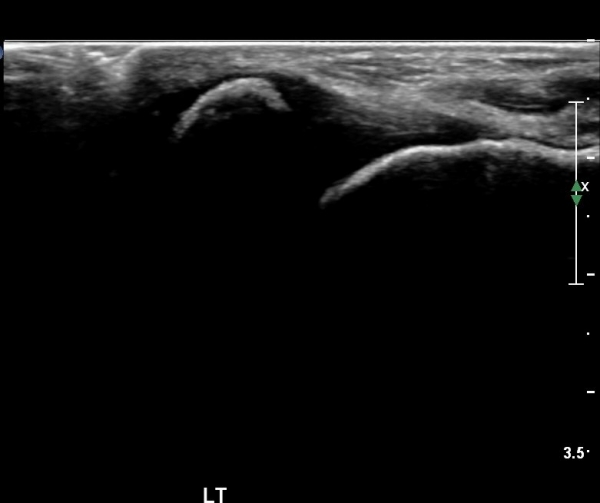

ÃÊÀ½ÆÄ °Ë»ç